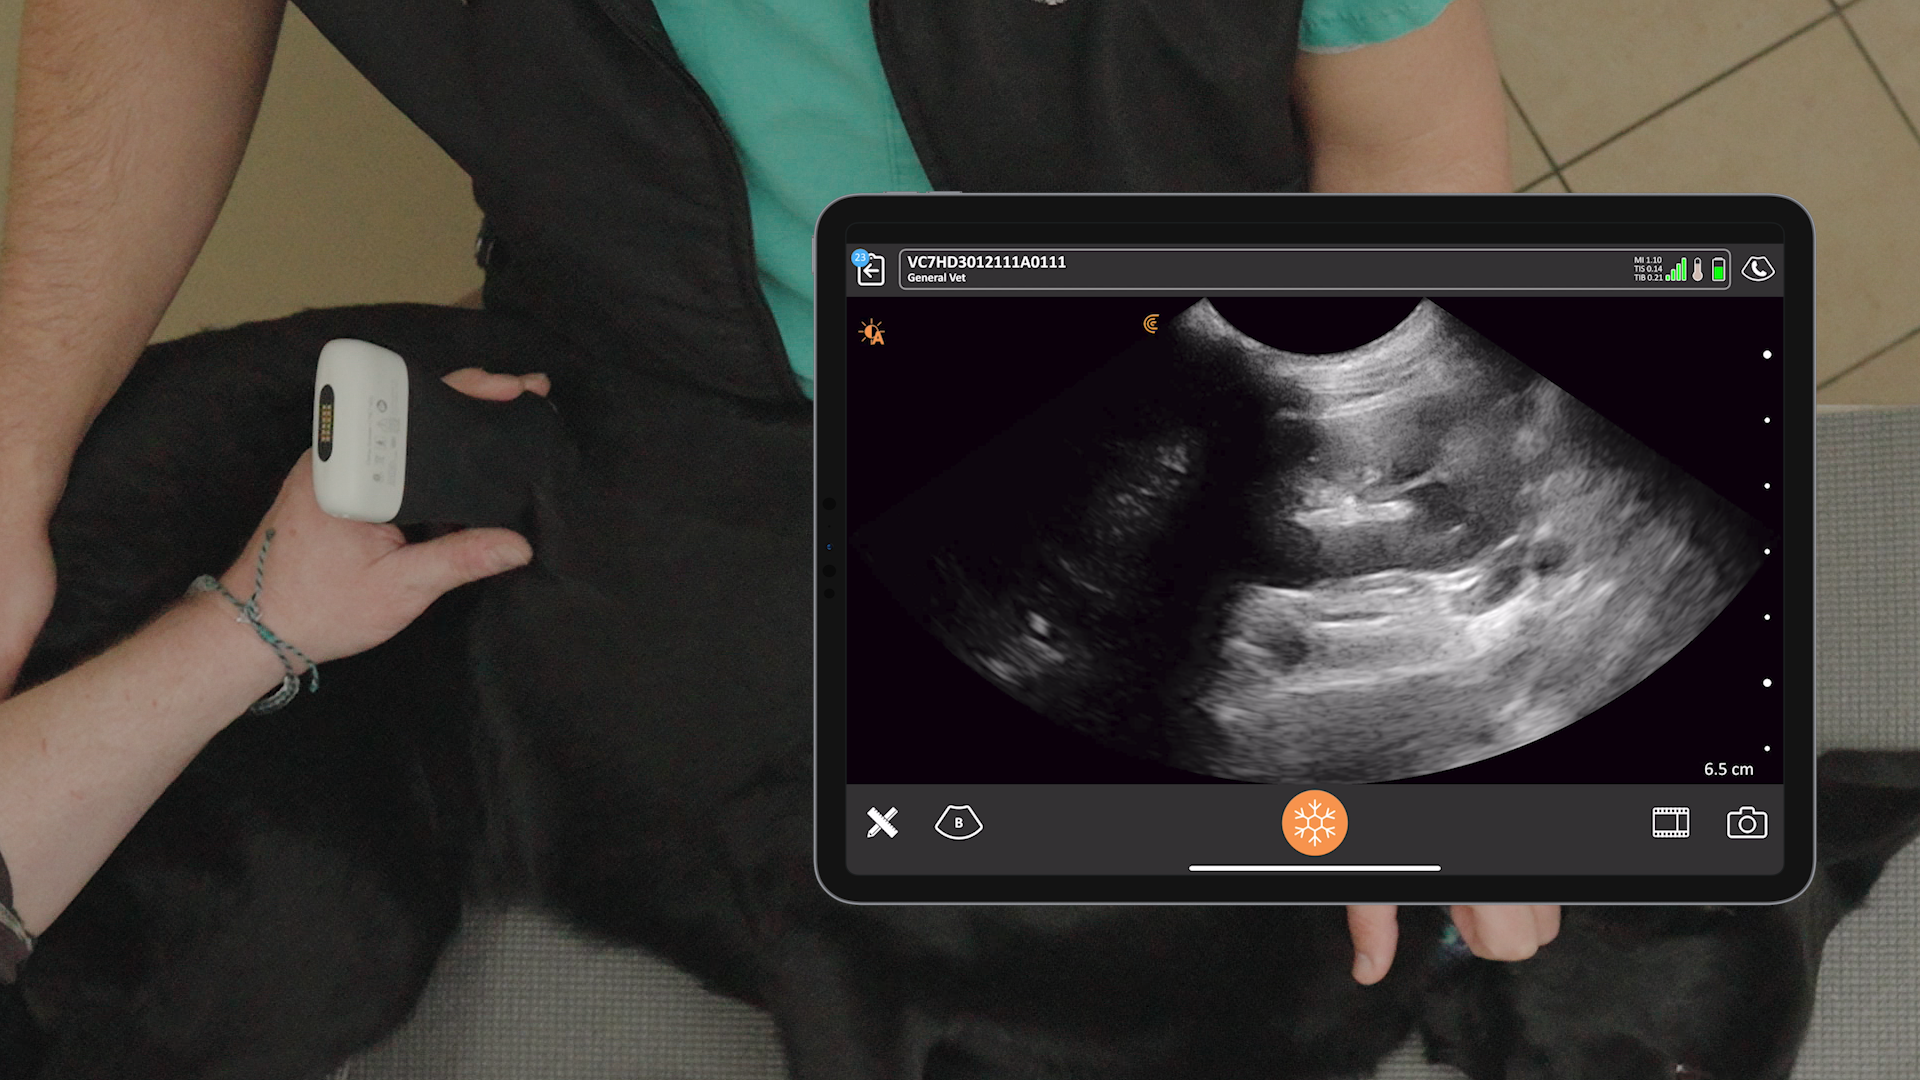

Join POCUS experts Dr. Soren Boysen and Dr. Serge Chalhoub as they teach rapid point-of-care ultrasound techniques to quickly evaluate the pleural space and lung in emergency and critical care situations.

Dog versus car usually doesn’t bode well for the dog and can result in a variety of injuries from pulmonary contusions to rib fractures. Radiographic examination may be difficult, making ultrasound a valuable diagnostic tool in the context of trauma-related respiratory distress, contributing to a timelier diagnosis for the best chance at stabilizing the patient.

In this dynamic and content-rich presentation, you’ll see helpful ultrasound image and video demonstrations of normal findings, with comparative pathological cases to fine tune your ultrasound image interpretation. This webinar will empower veterinary clinicians and technicians to enhance their diagnostic accuracy, expedite treatment decisions, and ultimately improve patient outcomes.

- Describe practical techniques for performing a focusedpleural space and lung ultrasound exam

- Utilize POCUS to distinguish between pneumothorax and pulmonary contusions